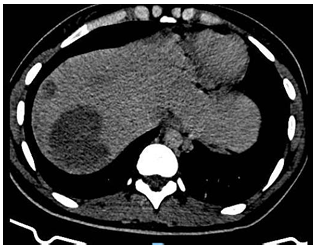

Debido a este hallazgo, con sospecha de enfermedad trofoblástica gestacional maligna se decide solicitar estudios de extensión TC tórax(Imagen 1), abdomen y pelvis(Imagen 2) en los cuales se evidencian múltiples lesiones focales en ambos campos pulmonares, destacándose por su tamaño, aquella ubicada en región anterior del campo pulmonar derecho, comprometiendo lóbulo medio y lóbulo superior, de 25mm. Sugieren valorar secundarismo. El hígado presenta múltiples lesiones focales heterogéneas, con realce con el contraste endovenoso, la mayor a nivel del segmento Vll, de 60mm, vinculables a secundarismo en primer término. Bazo de tamaño conservado, con lesión de semejantes características a las descritas en hígado, de 42mm, asimismo sugerente de secundarismo. Útero ausente en relación a los cambios descritos. Se observan aparentes engrosamientos nodulares a nivel del lecho quirúrgico, que realzan tras la administración de contraste EV y sugieren la presencia de implantes.

Imagen 2. TC abdomen (corte a nivel superior) al diagnóstico